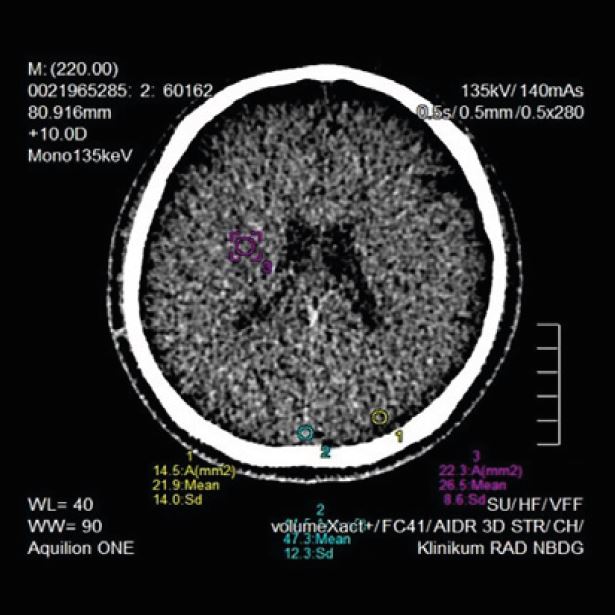

Наші КТ-сканери та програмне забезпечення для постобробки здатні створювати тривимірні зображення з високою роздільною здатністю, що, по суті, усуває попередні проблеми, пов’язані з візуалізацією перфузії. Обмеження часткового охоплення мозку КТ-перфузією було подолано завдяки введенню зонального детектора на Aquilion ONE та режиму "shuttle mode" в Aquilion Prime SP.

Унікальний двонаправлений нахил гентрі, зменшення металевих артефактів однієї енергії (SEMAR), Spectral Imaging і видалення кістки SURESubtraction усувають різні інші проблеми, які часто виникають під час візуалізації в неврології

4D перфузія всього мозку